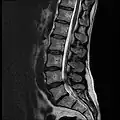

MRI lumbar spine with degeneration (sagittal T2 FRFSE) -